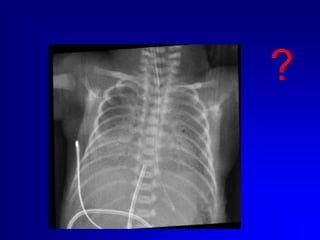

Eseguire sempre controllo radiografico o ecografico della posizione del catetere..

Eseguire semprecontrollo radiografico o ecografico della posizione del catetere..